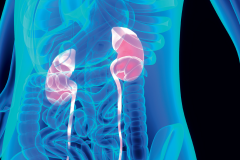

Polecamy też teksty poruszające klasyczne zagadnienia, jednak prezentujące nowe lub rozszerzone podejście do typowych problemów pacjentów. Należą do nich dolegliwości odcinka szyjnego, nerek, zmiany zwyrodnieniowe stawów kolanowych, a także dysfunkcja mięśni dna miednicy.